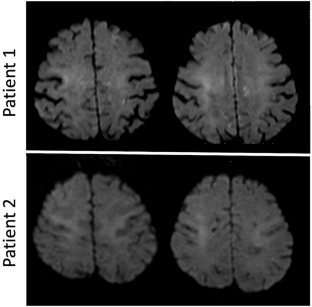

Neuronal intranuclear inclusion disease (NIID) is an autosomal dominant inherited neurodegenerative disease caused by NOTCH2NLC GGC repeat expansions. A high-intensity signal in the corticomedullary junction (CMJ) on magnetic resonance (MR) diffusion-weighted imaging (DWI) is a well-known characteristic of NIID. However, because of its diverse clinical symptoms and frequent presence of cerebral white matter hyperintensity (WMH) lesions on MRI, patients with NIID may be suspected of having other leukoencephalopathies. The aim of the present study was to identify patients with NOTCH2NLC GGC repeat expansions among those with undiagnosed leukoencephalopathies, recruited from NOTCH3-negative cerebral autosomal dominant arteriopathy with subcortical infarcts and leukoencephalopathy (CADASIL)-suspected and GFAP-negative Alexander disease (AxD)-suspected patients. Among 459 NOTCH3-negative CADASIL-suspected patients, 18 (3.9%) showed NOTCH2NLC GGC repeat expansions; however, among 40 GFAP-negative AxD-suspected patients, none exhibited such repeat expansions. On comparing 17 patients with GGC repeat expansions, whose clinical information was available, with 179 CADASIL probands previously reported by us, the former showed significantly higher frequencies of seizure (23.5 vs. 6.9%, respectively), WMH in the corpus callosum (92.9 vs. 9.2%, respectively), paravermis (21.4 vs. 2.7%, respectively), and middle cerebellar peduncle (21.4 vs. 3.4%, respectively), and DWI high-intensity signals in CMJ (61.5 vs. 1.4%, respectively). In conclusion, not only DWI high-intensity signals in CMJ, but also the WMH distribution, particularly a high frequency in the corpus callosum, and presence of seizures are useful for detecting NIID in patients with undiagnosed leukoencephalopathies.